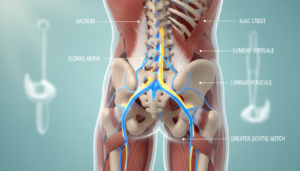

Anatomie und Ursachen: Verbindung von unterem Rücken, Becken und Nerven

Die Verbindung zwischen Becken und Wirbelsäule ist entscheidend für schmerzfreie Bewegung. Hier treffen verschiedene Strukturen zusammen.

Das Iliosakralgelenk bildet das Zentrum dieser Verbindung. Es überträgt Kräfte zwischen Oberkörper und Beinen.

Funktion des Iliosakralgelenks

Dein Kreuzbein verbindet die Lendenwirbelsäule mit dem Becken. Diese Stelle heißt Iliosakralgelenk.

Das Gelenk ist straff und beweglich. Es ermöglicht kleine Anpassungen bei jeder Bewegung. Langes Sitzen macht es steif.

Beteiligte Muskeln und typische Verspannungen

Die Muskulatur um das Becken arbeitet als Einheit. Verspannungen haben direkte Auswirkungen.

Der Piriformis-Muskel im Gesäß liegt über dem Nerv. Seine Verspannung kann Druck verursachen.

Verkürzte Hüftbeuger ziehen am Becken. Das belastet die gesamte Rückenmuskulatur.

Eine stabile Becken-Wirbelsäulen-Verbindung ist die Basis für schmerzfreie Bewegung.

Die Ursachen sind meist muskulär. Verspannte Muskeln, blockiertes Gelenk, Druck auf Nerven. Die Lösung heißt: Mobilisation und Dehnung.